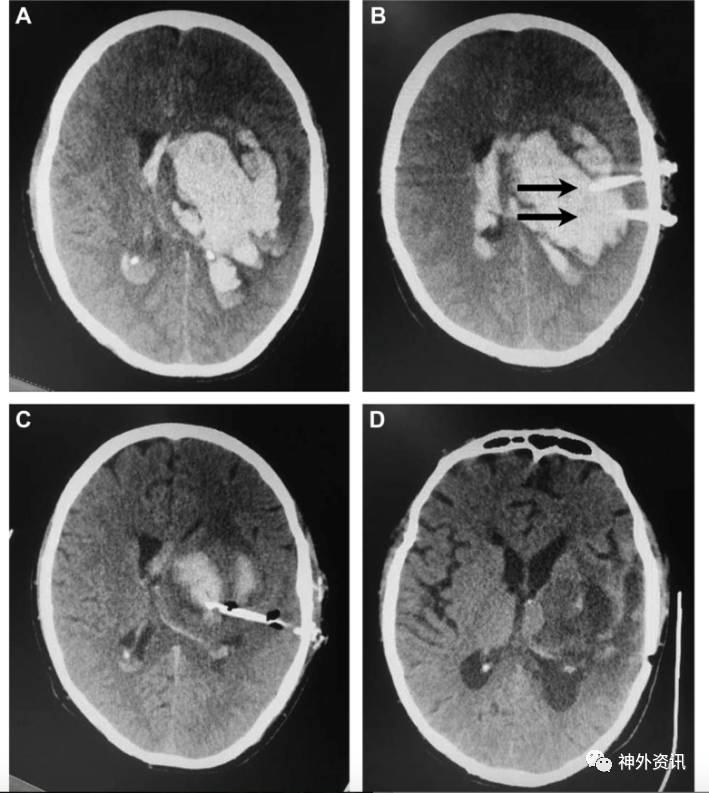

图2. 60岁男性患者,左侧基底节出血,血肿量约92ml;置两根引流管。